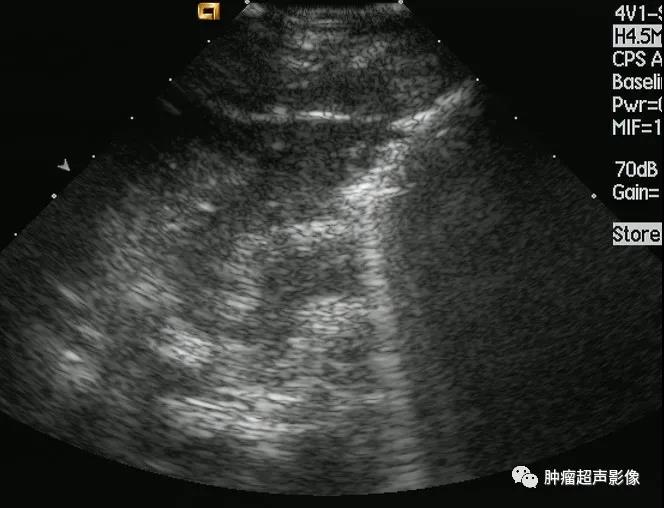

淋巴瘤是原发于淋巴结或淋巴组织的恶性肿瘤,分霍奇金淋巴瘤与非霍奇金淋巴瘤。淋巴结内多见,结外也可原发或受累,结外淋巴瘤临床表现复杂多样,误诊率极高,因淋巴瘤以化疗...